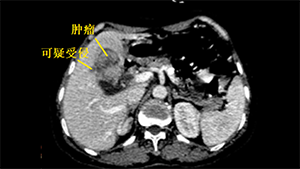

腹腔镜Ⅲb型肝门胆管癌根治术

作者:蔡翊 | 作者单位:湖南省人民医院

发布时间:2020-09-03 22:17:01